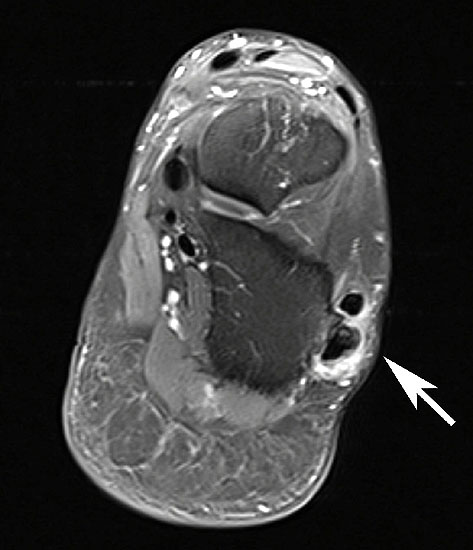

MRT mit KM bei Split der Peronaeus brevis Sehne in Höhe der Fibulaspitze

Abbildung 13

Klassischerweise beginnt eine Peronealsehnenruptur mit einem Distorsionstrauma. Bei dieser Verletzung kommt es zunächst zu einer Längsruptur (Peroneus-Split) der Peronaeus brevis Sehne in Höhe der Fibulaspitze. Bestehen nun Risikofaktoren wie eine persistierende Instabilität des Sprunggelenks oder ein bis zu diesem Zeitpunkt asymptomatischer Rückfußvarus, kommt bei jeder weiteren Distorsion zu einer Zunahme des Sehnenschadens bis hin zur vollständigen Kontinuitätsunterbrechung 38. Für das Peronaeus Split Syndrom gibt es kein klassisches Leitsymptom. Wichtig ist bei anhaltenden Beschwerden nach einem Distorsionstrauma an diese Differentialdiagnose zu denken und ein MRT mit Kontrastmittel zu veranlassen 39.